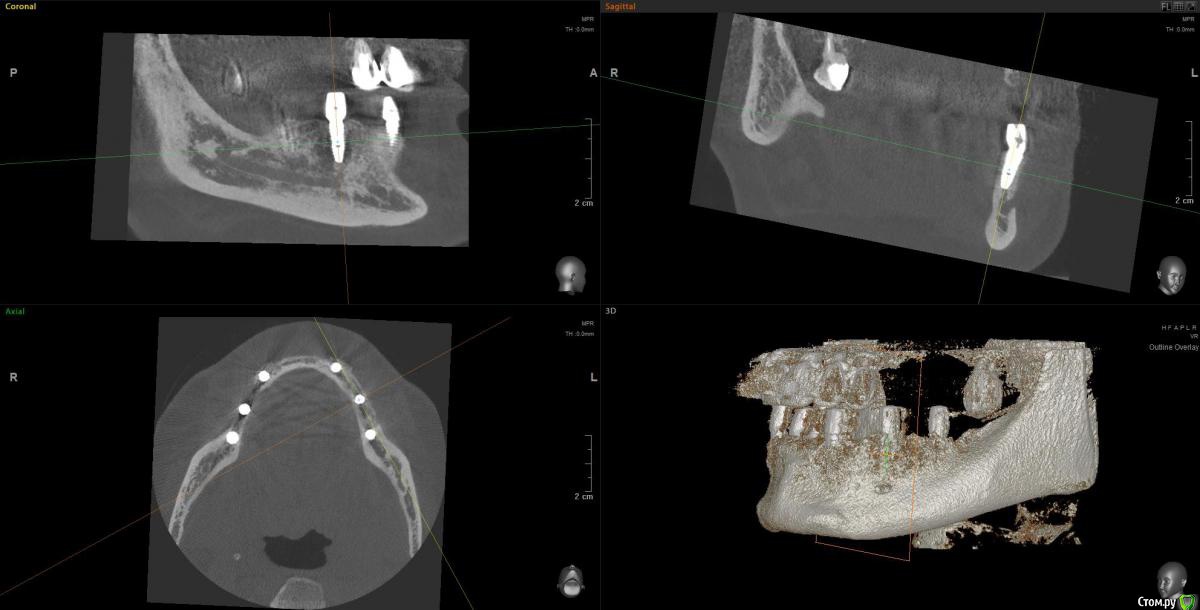

Kostoprav Опубликовано 14 июня, 2019 Поделиться Опубликовано 14 июня, 2019 Ксено+ауто +i prf, поверх титановых мембран перикард. кт через 5 мес.при и создании прикрепленки использовалась свиная дерма отечественного производителя 4 Ссылка на комментарий

vgraev Опубликовано 20 июня, 2019 Поделиться Опубликовано 20 июня, 2019 спасибо за клинический случай! скажите,пожалуйста, это сетки,фиксированные заглушками, или смарт билдеры со спейсерами? Ссылка на комментарий

Kostoprav Опубликовано 28 июня, 2019 Автор Поделиться Опубликовано 28 июня, 2019 спасибо за клинический случай! скажите,пожалуйста, это сетки,фиксированные заглушками, или смарт билдеры со спейсерами?сетки фиксировал спейсерами Ссылка на комментарий